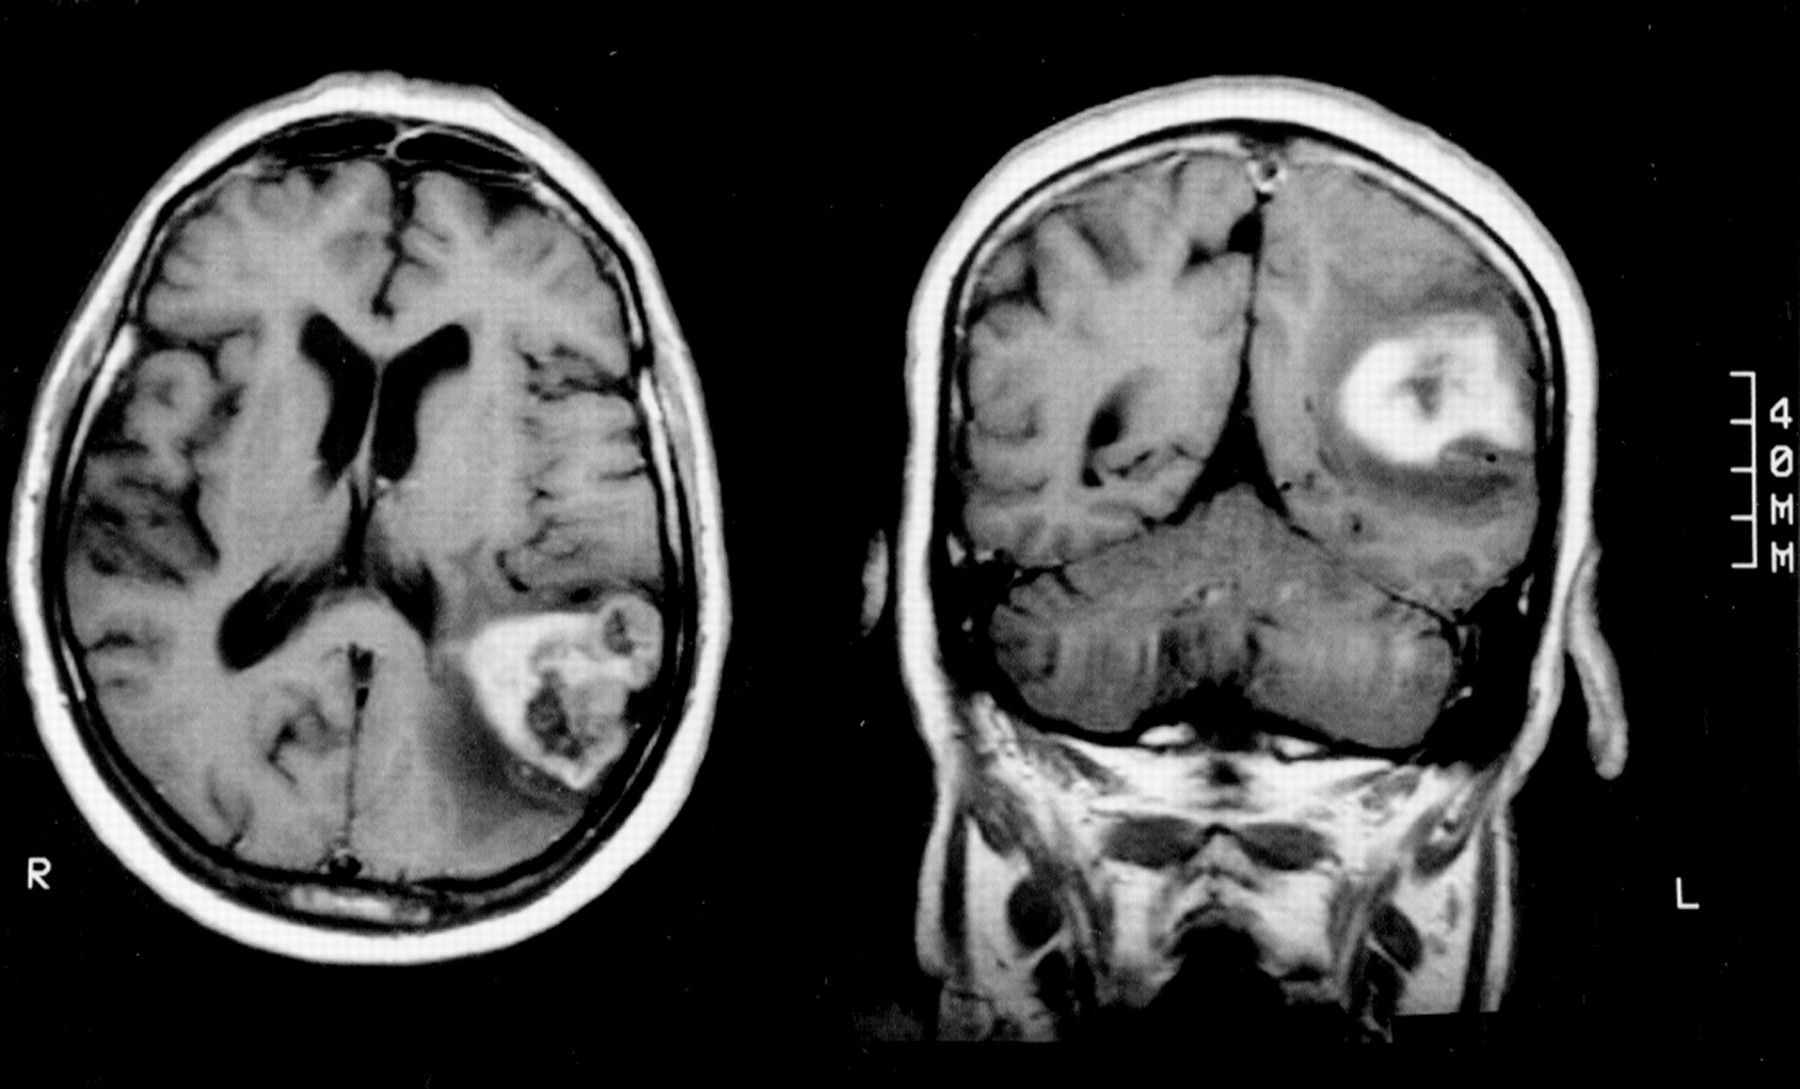

Gerstmann syndrome is a rare constellation of signs and symptoms attributed to brain tumor in the dominant parietal lobe of the brain. The condition is characterized by: - inability to calculate i.e., acalculia - inability to draw i.e., agraphia - loss of distinction between left and right side - inability to identify own or another's finger i.e., finger agnosia Reference: https://rarediseases.org/rare-diseases/gerstmann-syndrome/#:~:text=Gerstmann%20syndrome%20is%20a%20rare%20disorder%20characterized%20by%20the%20loss,inability%20to%20make%20the%20distinction Image via: https://jnnp.bmj.com/content/63/3/399